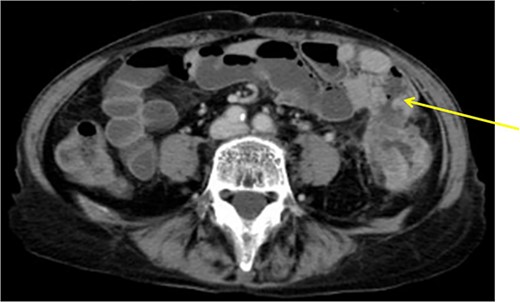

The operative time was 234 min, and the blood loss volume was 155 ml. Histopathological analysis revealed numerous lymph node metastases within the mesentery of the small intestine, and the patient was diagnosed with pT4b (small intestinal mucosa) N3 (28/41) M1 (small mesenteric lymph node 6/8) f Stage IV (TNM classification), nonsolid type (por2) adenocarcinoma, ly3, v2 (Fig. 4a and b). After receiving chemotherapy, she died 18 months after surgery.

(a, b) Descending colon cancer with small intestine invasion and fistula formation.